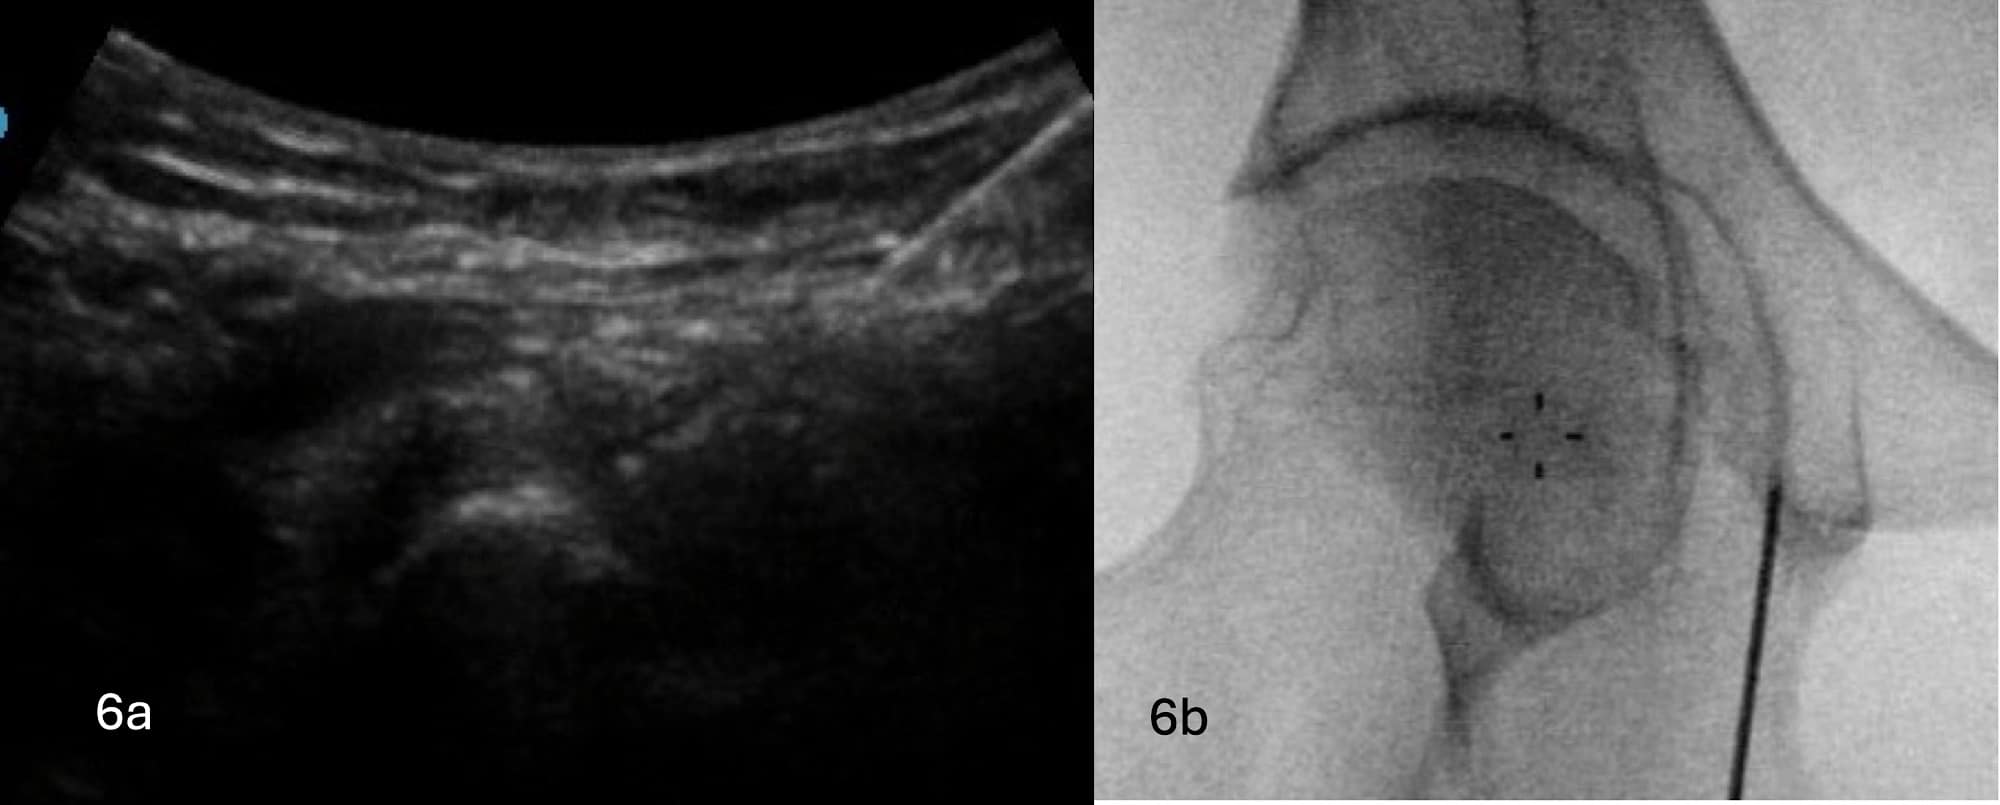

For the articular branches of the obturator nerve, author HM inserts the RF cannula sonographically from lateral to medial, caudad to cephalad, towards the IMA. The author positions the patient with slight hip external rotation and inserts the RF cannula in a more longitudinal fashion medially, through the adductor muscles, to avoid the femoral and lateral circumflex femoral arteries. Upon contact with bone, fluoroscopy is then used to ensure optimal placement of the RF cannula (see Figures 6A and 6B). Depending on the angle of insertion towards the IMA, the RF cannula may contact the bone further along the pubis and will need to be optimized. The author uses monopolar RF with two to three lesions with the RF cannula in slightly different angles on the IMA to ensure larger area of lesioning whereas the author uses cooled radiofrequency ablation.